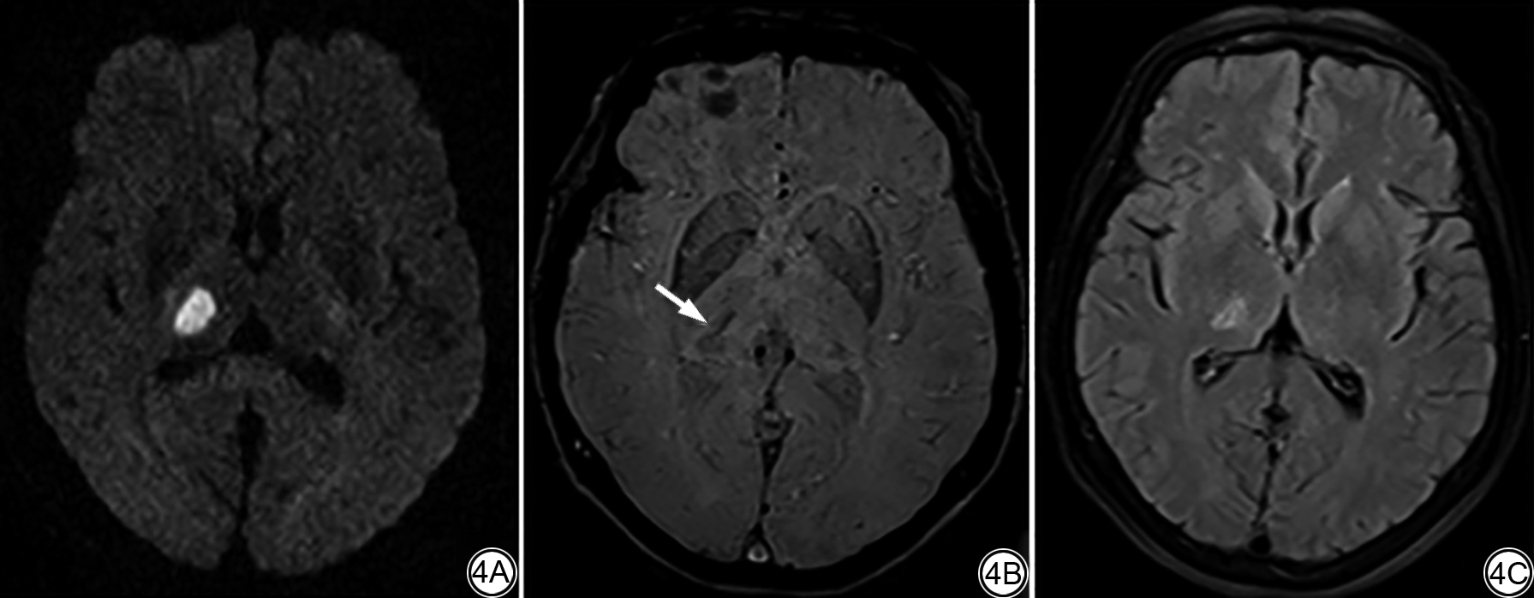

本研究共纳入105例RSSI患者,其中63例(60.00%)梗死灶演变为腔隙灶,34例(32.38%)梗死灶演变为WMH(非腔隙化),8例(7.62%)梗死灶消失(非腔隙化)(图1, 图2, 图3)。腔隙化组、非腔隙化组间年龄、高血压、糖尿病、高血脂、吸烟、入院卒中评分量表(National institutes of Health Stroke Scale, NIHSS)评分、随访MRI间隔时间、梗死灶部位、基线总WMH评分差异均无统计学意义(P>0.05,表1);腔隙化组、非腔隙化组间性别、初始DWI梗死灶直径、陈旧性腔隙灶数量差异有统计学意义(P<0.05,表1)。

图1  男,58岁,近期皮质下小梗死灶腔隙化。头颅DWI(1A)示左侧内囊梗死灶,随访4.5个月后,FLAIR(1B)及T2WI(1C)上演变为腔隙灶。

图2  女,41岁,近期皮质下小梗死灶演变为WMH。头颅DWI(2A)示右侧丘脑梗死灶,随访6个月后,FLAIR(2B)及T2WI(2C)上演变为WMH。

图3  男,51岁,近期皮质下小梗死灶消失。头颅DWI(3A)示中脑一梗死灶,随访3.6个月后,FLAIR(3B)及T2WI(3C)上病灶消失。DWI:弥散加权成像;FLAIR:液体衰减反转恢复;T2WI:T2加权成像;WMH:脑白质高信号。

Fig. 1  Male, 58 years old, recent small subcortical infarct lesions develop to cavities. DWI (1A) of the head image shows infarct in the left internal capsule, after 4.5 months of follow-up, the infarct lesion develops to cavitation on FLAIR (1B) and T2WI (1C).

Fig. 2  Female, 41 years old, recent small subcortical infarct lesions develop to WMH. DWI (2A) of the head image shows infarct in the right thalamus, after 6 months of follow-up, the infarct lesion develops to WMH on FLAIR (2B) and T2WI (2C).

Fig. 3  Male, 51 years old, recent small subcortical infarct lesions disappear. DWI (3A) of the head image shows infarct in the midbrain, after 3.6 months of follow-up, the infarct lesion disappears on FLAIR (3B) and T2WI (3C). DWI: diffusion-weighted imaging; FLAIR: fluid attenuated inversion recovery; T2WI: T2-weighted imaging; WMH: white matter hyperintensities.